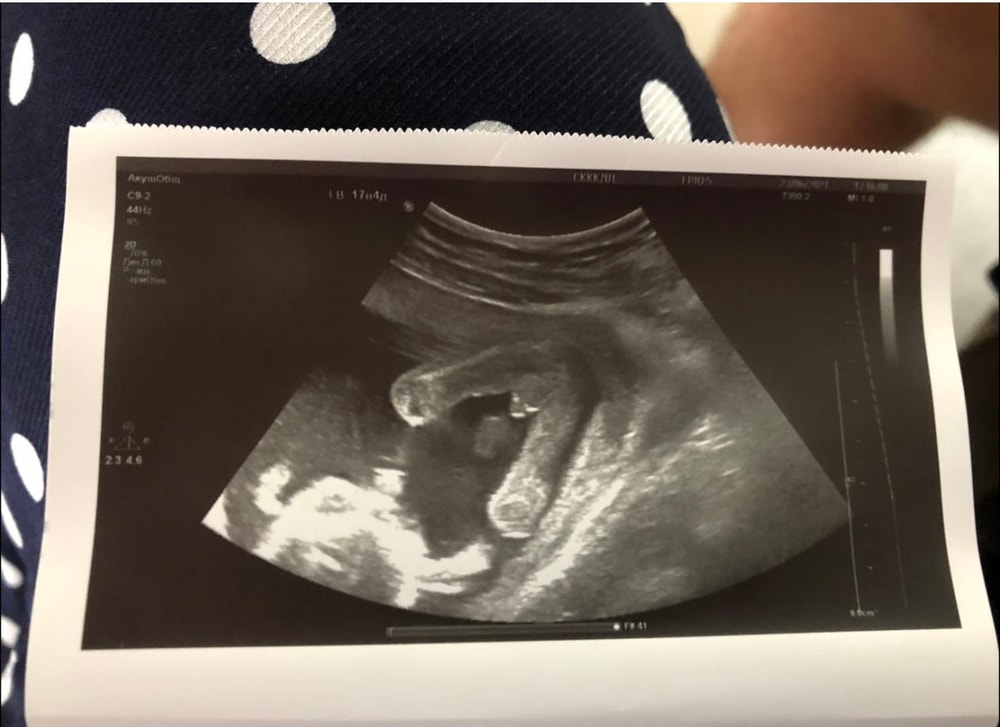

УЗИ, КТГ, доплерДевочки, на скрининге предложили девочку , ходила все эти недели думая , что там девченка, а по фото в 16+3 нашли писюнчик🤣🤣🤣

Ваше мнение,это точно пацан или все таки пока непонятно?

Похоже на мужские половые органы, да)

У дочки в 15 недель всё выглядело совсем иначе)